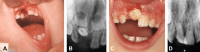

Background: Luxation injuries to the predecessors can cause sequelae in the permanent successors.

Results: Hypoplasia and malformations occurred more often in the 0-2-years group and were related to lateral luxation, intrusion, and avulsion injuries in the primary dentition. Demarcated and diffuse opacities occurred in all age groups and were related to subluxation, extrusion, lateral luxation, intrusion, and avulsion injuries. The risk was found to be more than seven times greater in trauma subgroups compared to controls.

Conclusion: The younger the child is at the time of traumatic dental injury and the more extensive the luxation injury is, the greater the risk of developing a sequela.